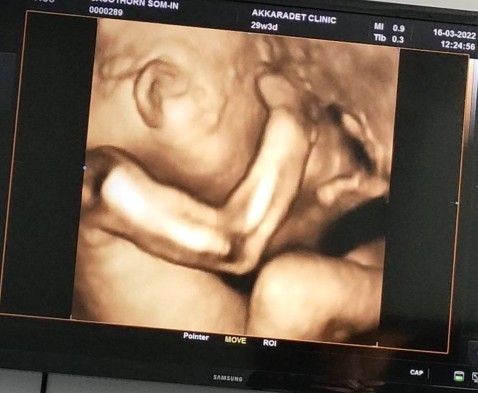

วันนี้ไปหาหมออายุครรภ์29week3dayค่ะ น้ำหนักน้องอยู่ในเกณฑ์ 1450กรัม แต่คุณหมอบอกช่วงนี้ต้องกลับหัวแล้ว เพราะน้องจะโตไวขึ้นในวีคหน้า ถ้าตัวโตจะกลับหัวยาก แต่ก็ถ้าไม่กลับหัวก็ต้องผ่าคลอดค่ะ ใจก็อยากคลอดธรรมชาติค่ะ #ท้องแรกค่ะ อายุย่าง39แล้ว ได้ลูกชาย กำหนด29พ.ค.65